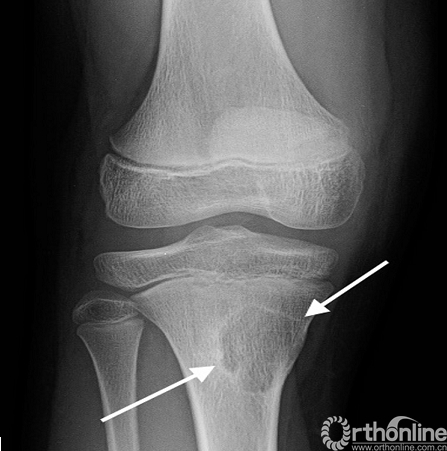

影像学特点:在X线上典型的表现为呈偏心,卵形或细长形,部分溶骨性的干骺端病变(图9)。其最常见的部位依次为股骨远端、胫骨近端、近端腓骨、远端胫骨,而股骨近端和肱骨近端罕见。非骨化性纤维瘤通常在一侧的骨皮质上呈膨胀、偏心性生长。腓骨例外,因骨的直径小而使病变呈成中央型生长。随着年龄增长,其自然病程表现为离骺板最远的部位首先被骨化(图10)。

图9.非骨化性纤维瘤(箭头),主要为干骺端皮质部位的溶骨性病损,边缘环状硬化,多见于骨骼未成熟的患者。

图10.愈合的非骨化性纤维瘤(箭头),偏心的干骺端病变已经大部分重新骨化,远离生长板的部位密度更高,可以看到典型的皮质膨胀和重塑。